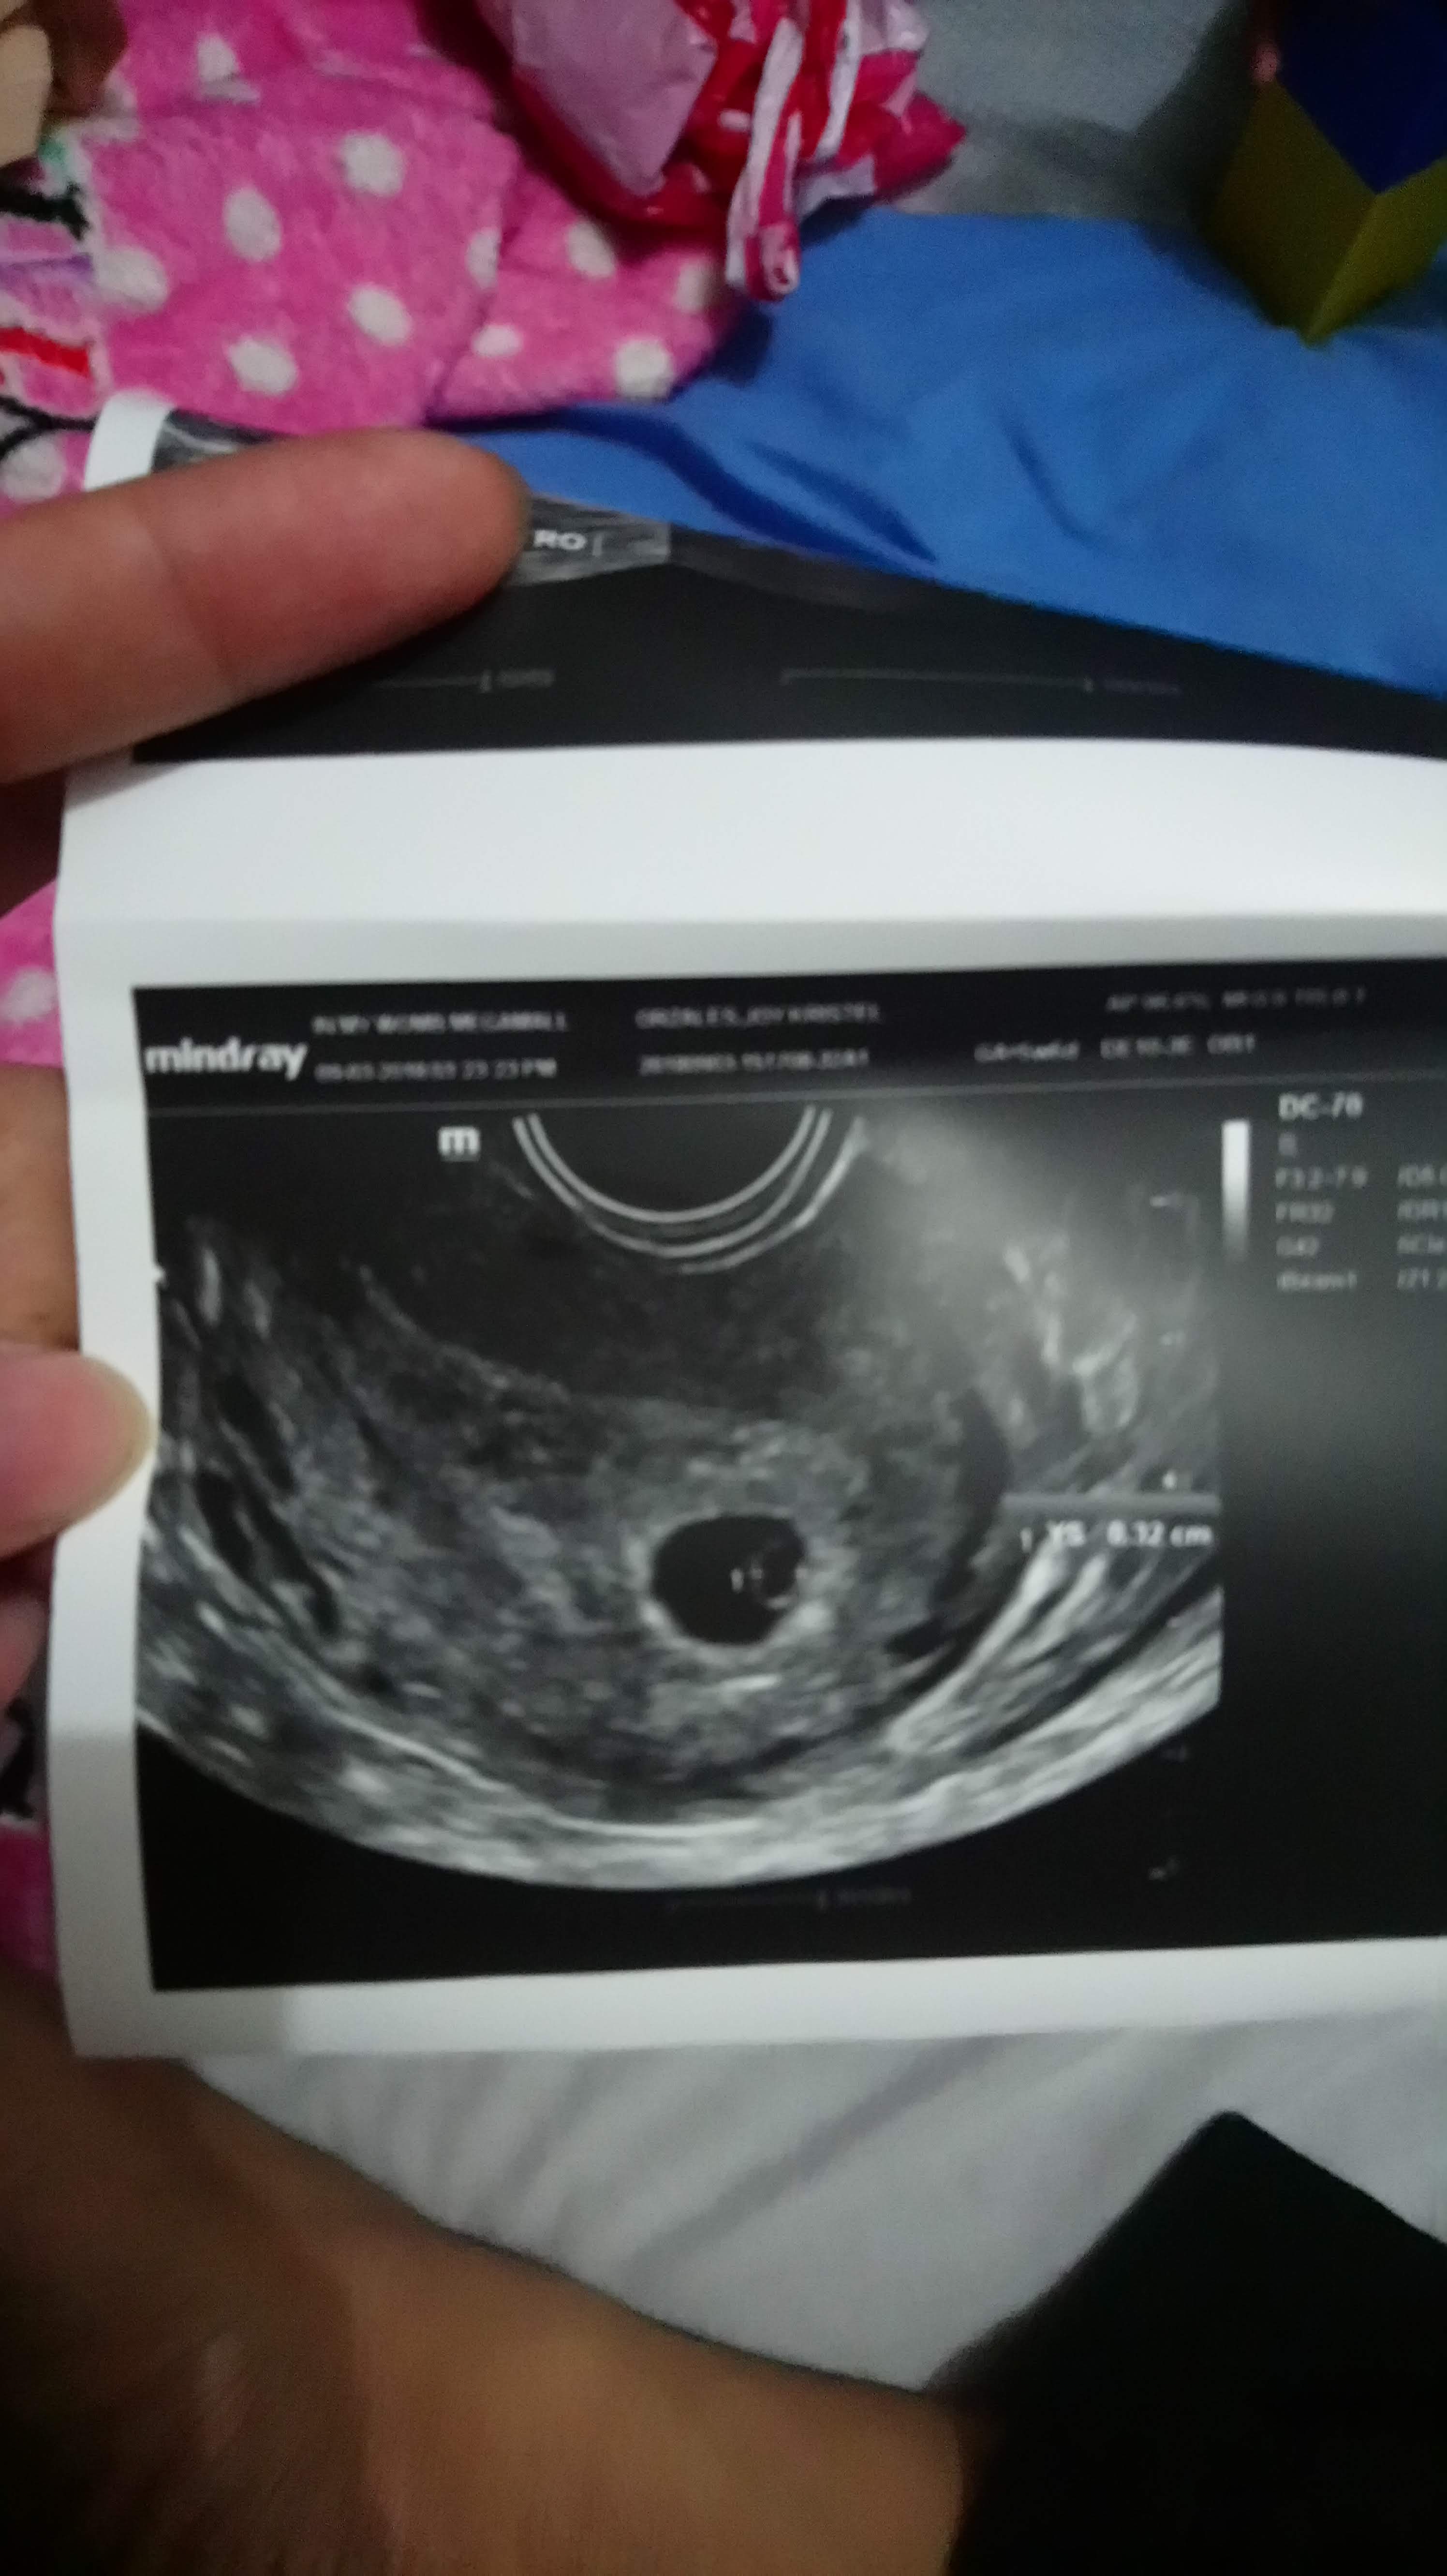

And finally, we were able to get an ultrasound since I need to get a clearance before going to Baguio. I was 5 weeks here.